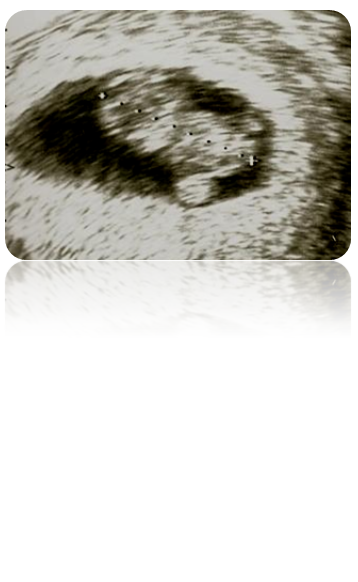

Ecografia para datação precoce no 1º trimestre

- avaliar viabilidade

- avaliar número de embriões/ fetos e corionicidade (nos casos de gravidez múltipla)

- datação precoce